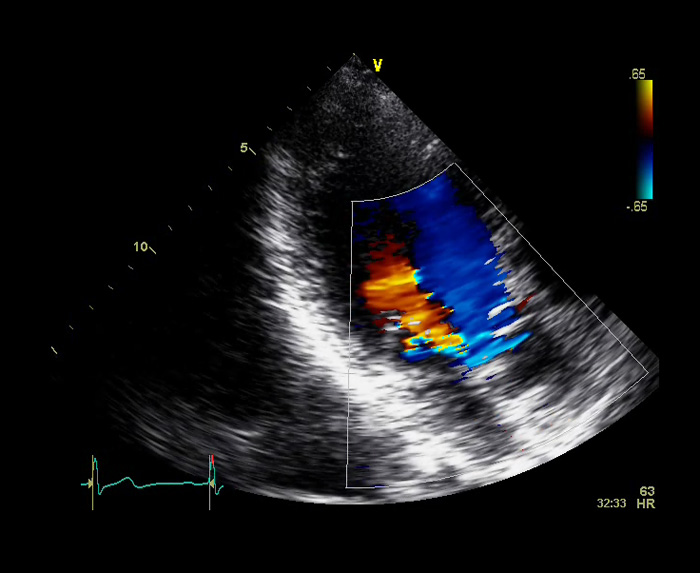

On a normal aorta valve you have three flaps which prevent the blood from leaking back into your heart when it beats. My heart is what they call bicuspid meaning I only have two of the three flaps which leaves a hole; quite a visible hole.